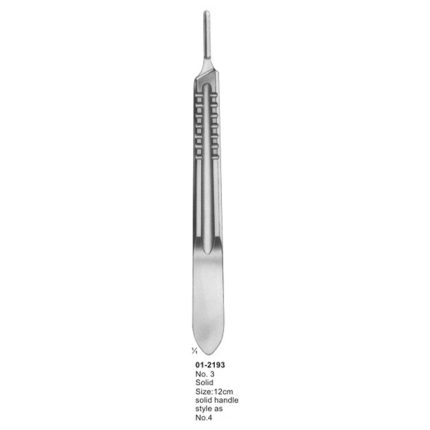

Collin Measuring Instruments 125 mm

Size: 125 mm

Life Time Guarantee

100% Quality assured by Complying FDA, CE and ISO Standards from first to last step of Production

Medical Grade Supper Quality Raw materials are used to Produce This Product.

SKU:

LS-084

Category: Measuring Instruments

Tags: Calipers, Collin Measuring Instruments, Dental, Examination Instruments, Instruments, Measuring Devices, Measuring Instruments, Medical Calipers, Surgical, Surgical Calipers, Surgical Measuring Instruments

Material: 100% Stainless Steel

Description

Collin Measuring Instruments 125 mm

Size: 125 mm

Druck Pressure 72 kg

Life Time Guarantee

100% Quality assured by Complying FDA, CE and ISO Standards from first to last step of Production

Medical Grade Supper Quality Raw materials are used to Produce This Product.